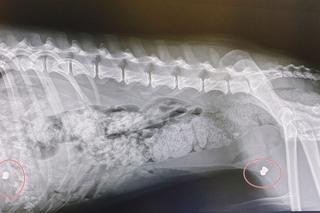

Na szczęście jakiś grzybiarz znalazł go i przywiózł do Fundacji ADA w Przemyślu (woj. podkarpackie). Tamtejsi weterynarze najpierw wyciągnęli kleszcze i przebadali psa. Potem zrobili mu zdjęcie RTG, które pokazało, że zwierzę jest podziurawione od śrutu. Psiak dostaje lekarstwa na wzmocnienie, a gdy odzyska siły – przejdzie operację.Jak tylko będzie na tyle silny, by można było go uśpić, wykonamy zabieg i wyciągniemy kule. To bestialstwo, w jaki sposób został potraktowany przez człowieka – mówił weterynarz Radosław Fedaczyński.